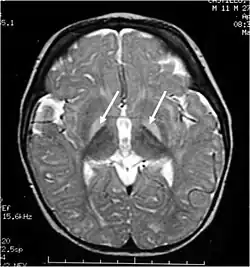

![]() Obraz MRI T2-zależny głowy pacjenta z żółtaczką w przebiegu niedoboru dehydrogenazy glukozo-6-fosforanowej uwidacznia hiperdensyjne ogniska w jądrach podkorowych | |

Żółtaczka jąder podkorowych (łac. kernicterus, nazywana też encefalopatią bilirubinową[1]) – choroba spowodowana uszkodzeniem jąder podstawnych i móżdżku wywołanym bilirubiną (która w nieznany sposób działa neurotoksycznie[2]) w przebiegu ciężkiej żółtaczki u noworodka[3][2][4]. Choroba ta może prowadzić do niepełnosprawności intelektualnej, padaczki, porażenia mózgowego i niedosłuchu czuciowo-nerwowego, a w niektórych przypadkach także do śmierci[2]